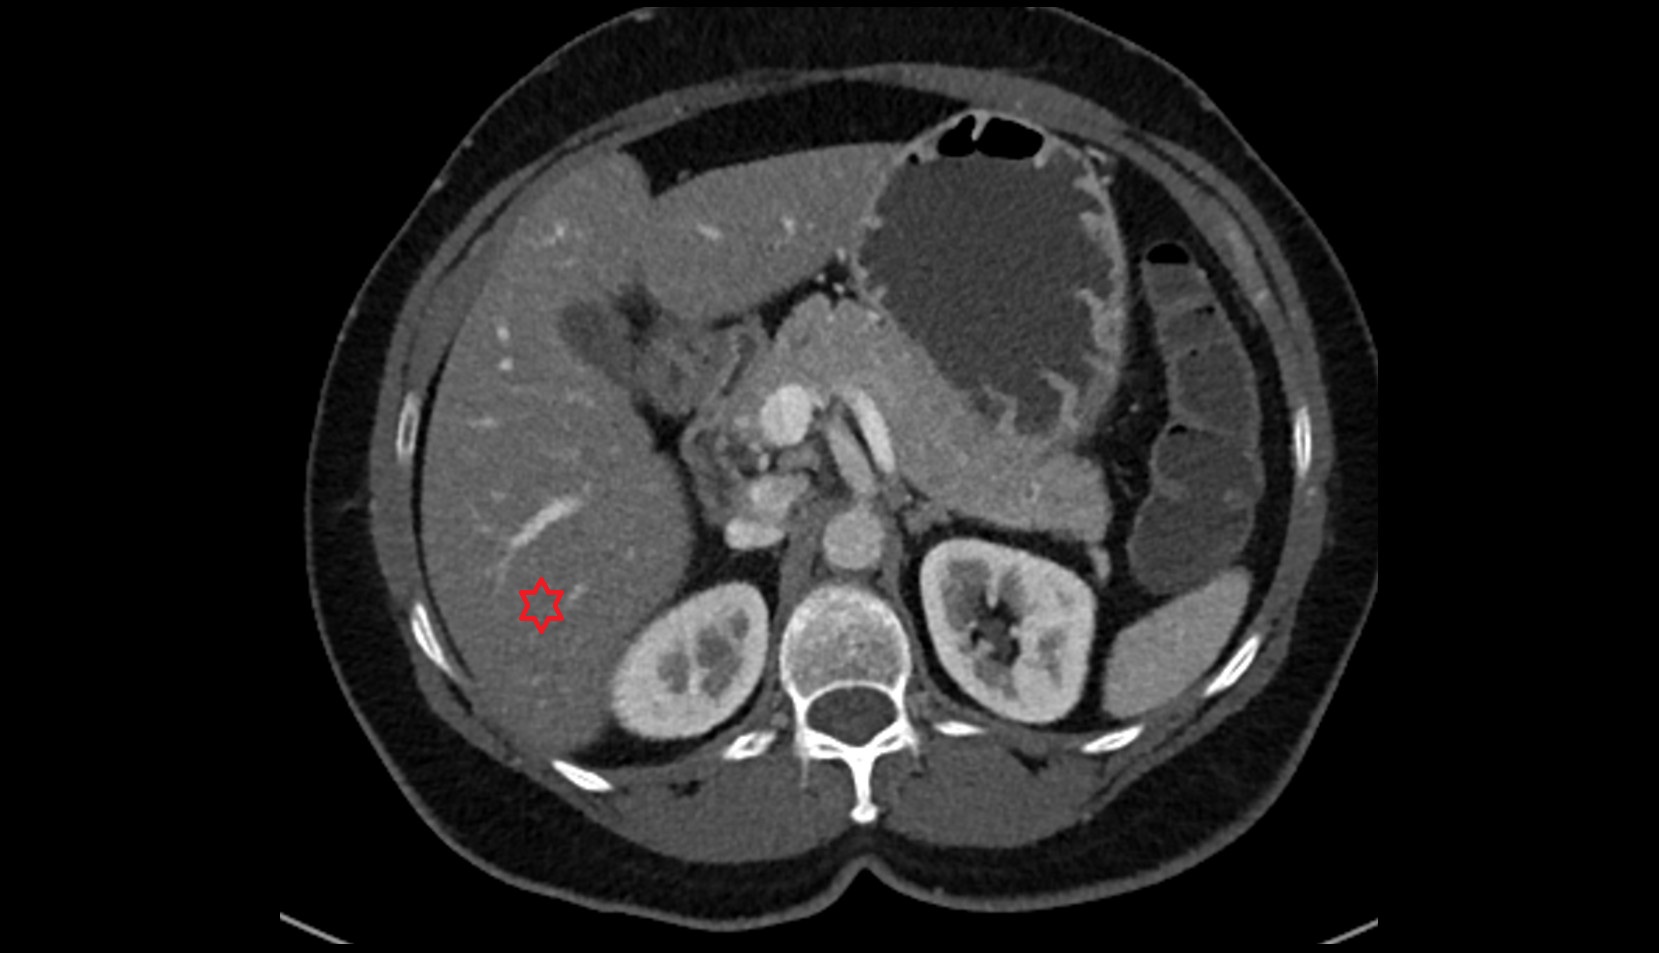

CT image

Liver right posteroinferior segment — Segment VI CT axial image